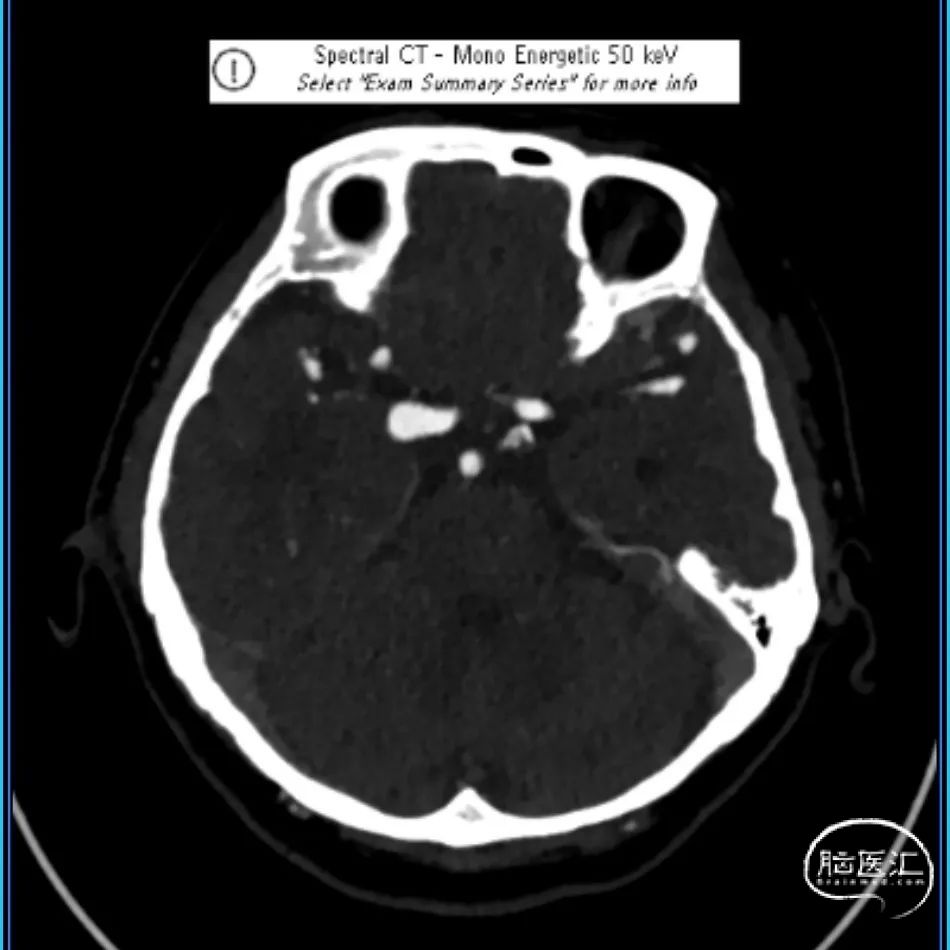

简要病史:患者近2周前体检行核磁MRI检查发现右侧颈内动脉动脉瘤,进一步完善头颅CTA检查明确为右侧颈内动脉C7段动脉瘤。

CTA:右侧颈内动脉C7段动脉瘤。

老年女性患者,检查发现右侧颈内动脉C7段大动脉瘤,动脉瘤直径大于10mm,形态不规则,宽颈,手术指征明确,既往高血压、肿瘤病史,首选微创介入手术,术中造影证实动脉瘤直径大于10mm,绝对宽颈,形态不规则,局部仔瘤改变,右侧脉络膜前动脉从瘤体发出;微创介入血流导向装置是较优选择。